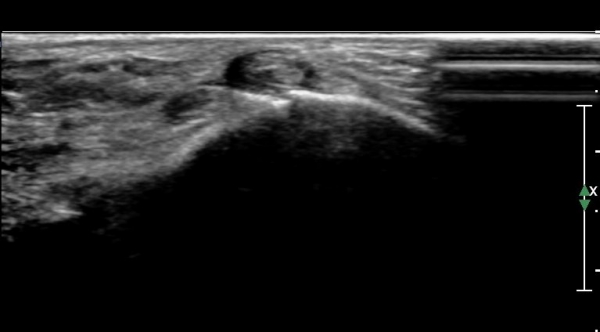

Á¾°ñºñ°ñÀδë Á¾´Ü¸é°Ë»ç¿¡¼­ °Å°ñÇϰüÀýÀÇ ¼ö¾×Àú·ù(Á¾°ñºñ°ñÀÎ´ë ½ÉºÎ ¼ö¾×Àú·ù)°¡

°üÂûµÈ´Ù(»çÁø 4).